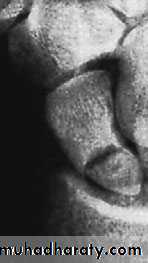

1-Avascular necrosis The proximal fragment may die,especially with proximal pole fractures, and then at 2–3 months it appears dense on x-ray.2-Non-union By 3 months it may be obvious that the fracture will not unite with sclerosis and cavitation. Bone grafting with compression screw should be attempted, especially in the younger, more vigorous type of patient, because this probably reduces the chance of later, symptomatic osteoarthritis.